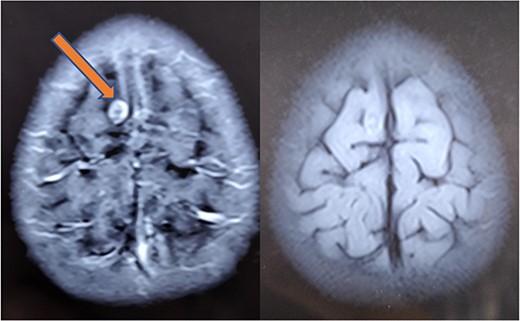

At 1-month follow-up, the patient had complete resolution of pain and swelling. Local USG back showed no evidence of any remnant lesion. At the 6-month follow-up, an MRI of the brain was done that showed a major reduction in the size of the lesion and resolution of perilesional edema (Fig. 7). At 1-year follow-up, the patient was found to be completely symptom-free, managing his activities of daily life, very well.

Repeat MRI at 6 months showing resolved changes with reduction in size of the lesion with resolution of perilesional edema.